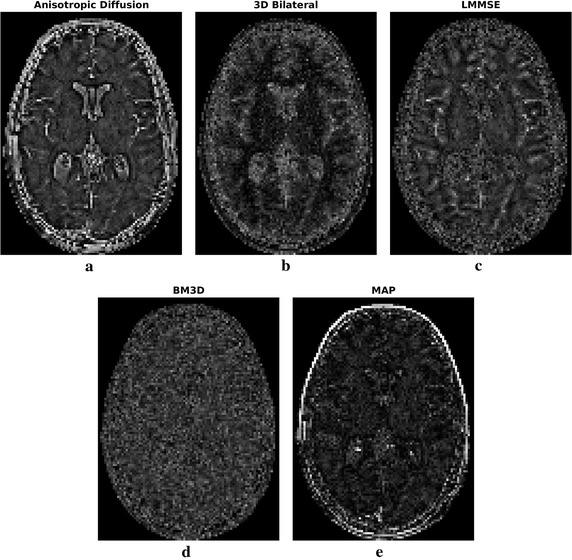

The method exploits Markov random fields in order to implement a 3D maximum a posteriori estimator of the image. Due to the local nature of the considered model, the algorithm is able do adapt the smoothing intensity to the local characteristics of the images by analyzing the 3D neighborhood of each voxel. The effect is a combination of details preservation and noise reduction. The algorithm has been compared to other widely adopted denoising methodologies in MRI. Both simulated and real datasets have been considered for validation. Real datasets have been acquired at 1.5 and 3 T. The methodology is able to provide interesting results both in terms of noise reduction and edge preservation without any supervision.

该方法利用马尔可夫随机场来实现图像的三维最大后验估计器。由于所考虑模型的局部性质,该算法能够通过分析每个体素的三维邻域,使平滑强度适应图像的局部特征。效果是细节保留和降噪的结合。该算法已与MRI中其他广泛采用的去噪方法进行了比较。模拟数据集和真实数据集均已用于验证。真实数据集是在1.5T和3T下采集的。该方法能够在无需任何监督的情况下,在降噪和边缘保留方面提供有趣的结果。